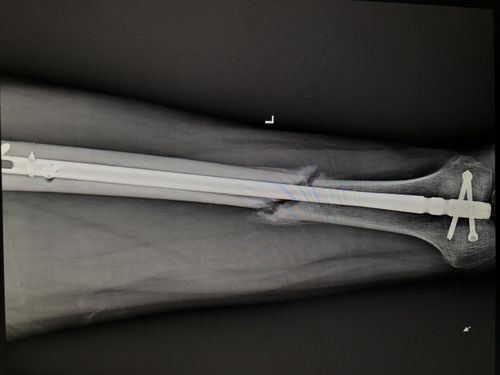

术后6个月见少量骨痂

术后5周骨折处可见骨痂形成

胫腓骨骨折长骨痂图片

小腿骨折骨痂长满图片